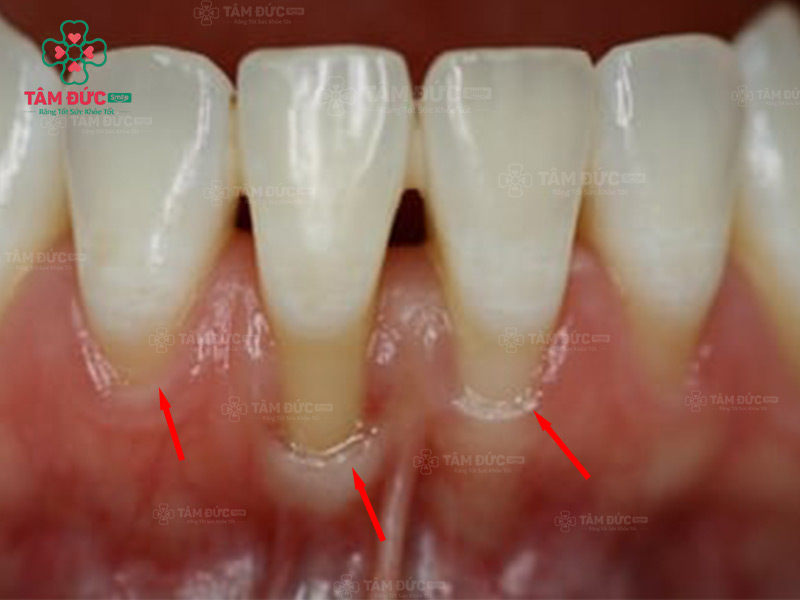

Tụt lợi là hiện tượng vùng lợi bao quanh chân răng bị tách khỏi chân răng rồi dịch chuyển xuống phần cuống răng. Tụt lợi sẽ làm thân răng bị lộ ra ngoài. Vấn đề này thường chỉ xuất hiện ở 1 vài răng, có thể xảy ra ở hàm trên hoặc hàm dưới.

Quý khách có thể nhận biết tụt lợi bằng mắt thường vì vùng lợi bị rút sâu xuống phía dưới, làm cho cổ răng lộ ra. Tuy nhiên, tụt lợi hàm dưới làm Quý khách khó phát hiện hơn, vì môi dưới đã che lấp toàn bộ chân răng và lợi. Tụt lợi sẽ làm ảnh hưởng nghiêm trọng đến thẩm mỹ nụ cười, làm cho răng nhạy cảm và suy yếu dần.

Tụt lợi làm lộ chân răng

3.3. Làm cho răng trông dài hơn

Vùng lợi xung quanh bị tụt xuống sẽ làm cho thân răng trồng dài hơn. Răng nhạy cảm rất dễ bị bám màu hoặc tạo thành kẽ hở lớn với răng còn lại. Điều này sẽ làm ảnh hưởng nghiêm trọng đến thẩm mỹ nụ cười.

Răng có vẻ dài hơn khi Quý khách bị tụt lợi chân răng